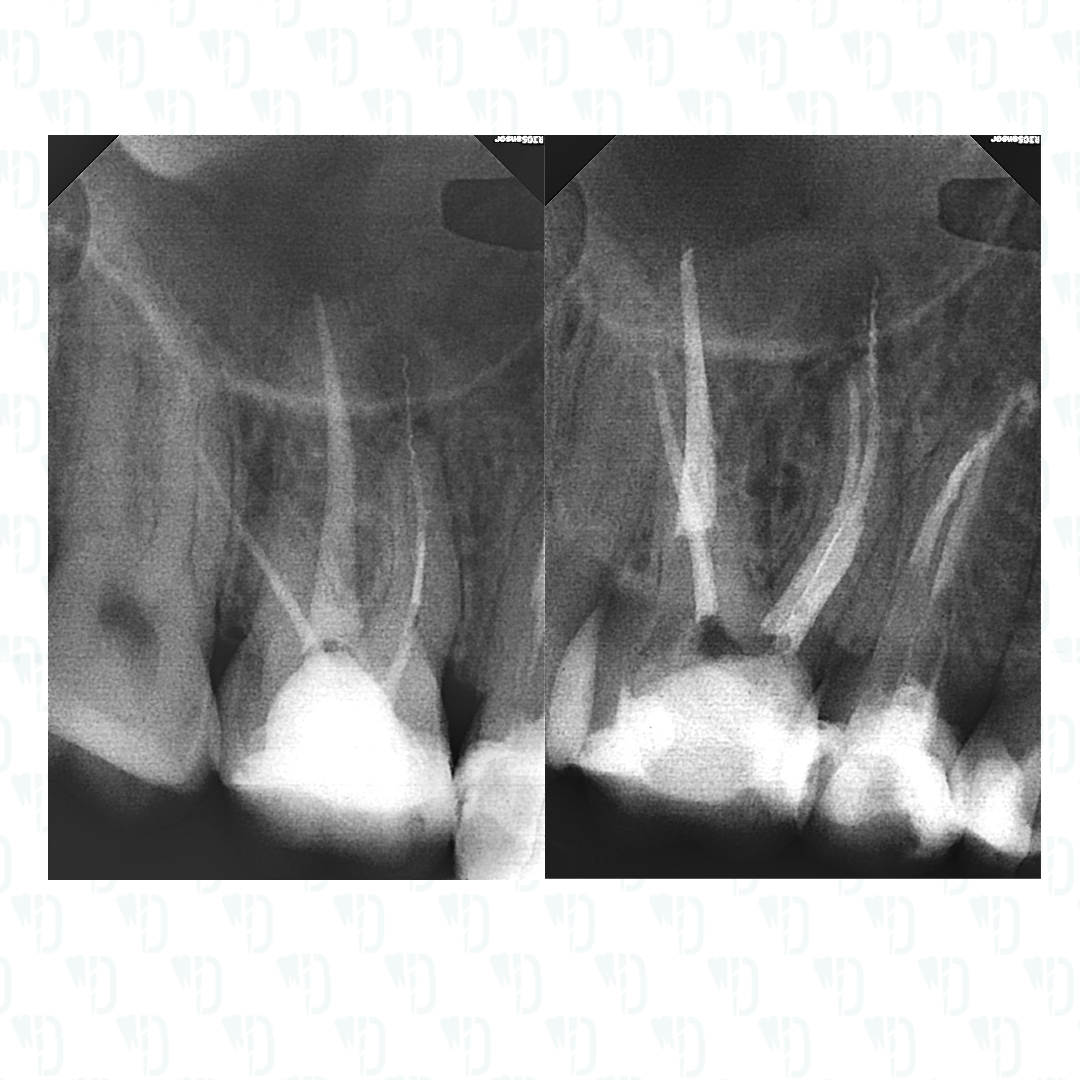

Хронический апикальный периодонтит.

В мезиальном корне два фрагмента инструментов. Подготовка к ортопедии.

Все по классике - дистальный 35.04, небный 45.02.

Мб2 30.05. Мб1 35.04 после извлечения фрагмента.

В мб корне петенси получил, за спиралью лезть даже не планировал. Выстрельнет - АМХ